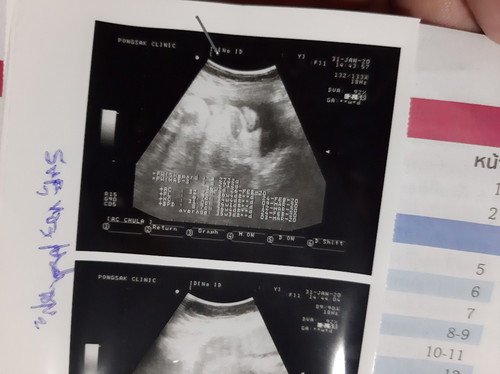

แม่ไปอัลตร้าซาวด์เมื่อวันที่ 31/1/20 อายุครรภ์ได้ 36w+2d แต่ในสมุดสีชมพูหมอเขียนกำหนดคลอด 12/3/20 สรุปเชื่ออันไหนได้คะ

นับตามประจำเดือนครั้งสุดท้ายค่ะหรือไม่ก็ก็สาวเฉพาะช่วงท้องอ่อนๆ ถ้าอัลตร้าซาวด์ช่วงหลังๆ จะประเมินตามขนาดเด็ก